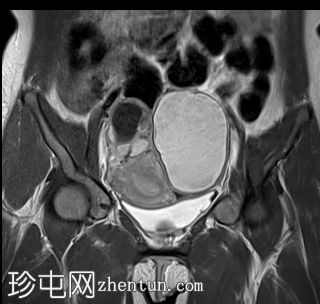

冠状位

6.jpg

T2加权像

左侧卵巢可见一巨大、无强化囊性病变。该病变壁薄,在T1加权像和T1脂肪抑制像上呈均匀高信号,在T2加权像上呈独特的阴影状,符合子宫内膜异位囊肿的特征。值得注意的是,该病变可见两个增强灶,但未见内部实性成分或对比增强。

此外,右侧卵巢内数个小的、无强化囊性病变表现出类似的信号特征,这也符合子宫内膜异位囊肿的特征。

双侧卵巢向内侧移位,形成“接吻卵巢征”。

子宫、双侧卵巢和直肠因挛缩性粘连/纤维带而靠近,形成近期描述的深部盆腔子宫内膜异位症的“三叶草征”。

双侧卵巢出血性囊肿提示双侧子宫内膜异位囊肿,也称为巧克力囊肿。双侧卵巢位置接近,被称为“接吻卵巢”,这是由于粘连、子宫圆锥韧带和卵巢圆韧带增厚以及卵巢、直肠和子宫呈三叶草状排列所致,提示盆腔子宫内膜异位症。